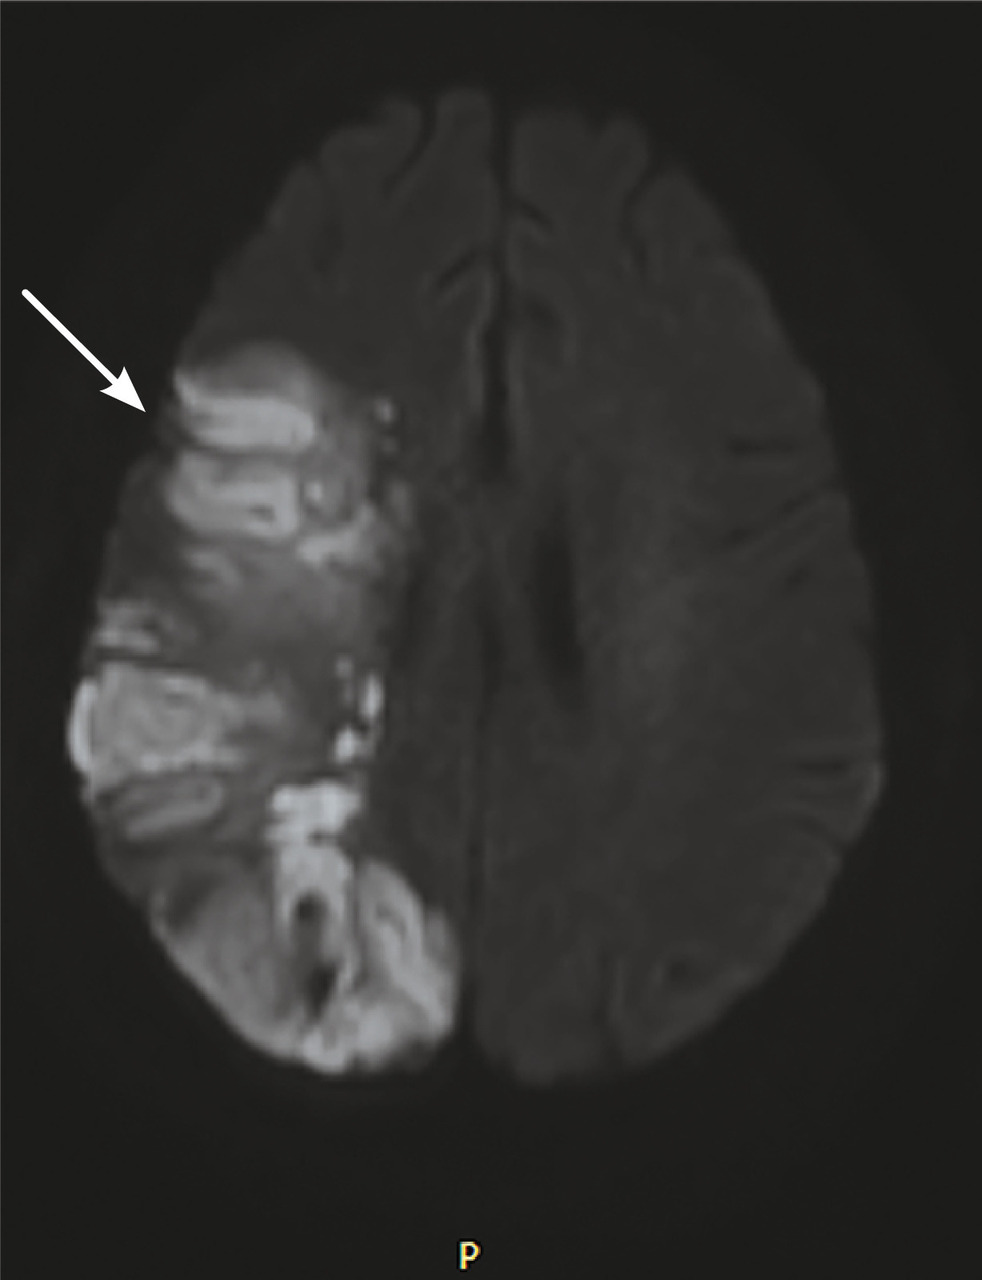

Cette femme de 45 ans était admise aux urgences à la suite d’une hémiplégie gauche. Une imagerie par résonance magnétique (IRM) cérébrale montrait un accident vasculaire cérébral ischémique aigu du territoire de l’artère cérébrale moyenne droite (fig. 1 ) avec occlusion de l’artère carotide droite. Par ailleurs, il y avait un comblant otomastoïdien droit (fig. 2 ) avec collection abcédée parapharyngée homolatérale (fig. 2 ) et thrombose de la veine jugulaire interne droite étendue au sinus sigmoïdien et latéral (fig. 3 ). Après 21 jours d’antibiothérapie intraveineuse combinée à l’anticoagulation, l’IRM de contrôle montrait une recanalisation de la carotide interne et de la veine jugulaire interne.